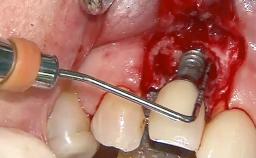

In this case, Nicola Zitzmann describes the sudden loss of a previously well-osseointegrated implant that had been in healthy function for 5 years. The case includes recommendations for occlusion and function of implant restorations. A 74-year-old patient had received implant-fixed dental prostheses in the maxilla in 2008, and in the right mandible three years later. His tooth loss was mainly related to recurrent caries associated with hyposalivation as a potential side effect of his cholesterol-lowering medication.